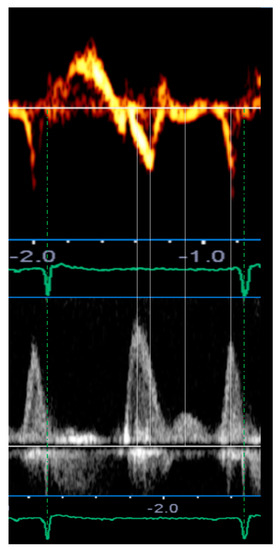

| Mid-diastolic transmitral flow velocity (L wave) | Distinct forward flow velocity after E wave with peak velocity ≥ 20 cm/s | Apical four-chamber view, sample volume at the tips of mitral leaflets with PW Doppler |

| Mid-diastolic mitral valve motion (L motion) | Mid-diastolic opening and closing motion of the mitral valve | Parasternal long-axis view M-mode along the line-cutting mitral valve |

| Mid-diastolic mitral annular velocity (L’ wave) | Distinct basilar–apical tissue velocity after E’ wave present in all cardiac cycles * | Apical four-chamber view, sample volume at septal and lateral mitral annular corners (TDI and PW Doppler) |